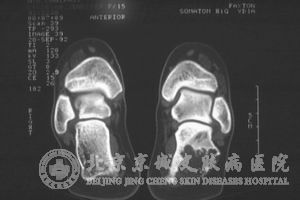

软纤维瘤属于良性肿瘤,临床上通常是采用组织病理进行诊断。但是需要与神经纤维瘤,多发性小的脂溢性角化病, 痣,结缔组织病,纤维上皮瘤进行鉴别诊断。

通过组织病理的切片检查我们发现,软纤维瘤万网是由于多度增生的表皮围绕着疏松结缔组织,进而演变成为一类结缔组织蒂,如果是囊袋形状的乳头瘤往往他们的表皮会变成扁平。